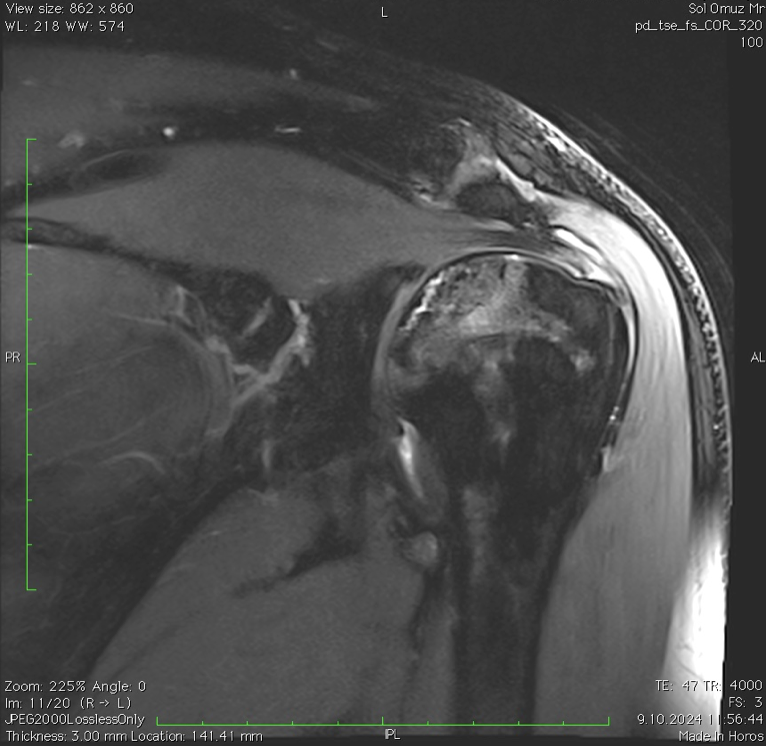

- Tanı: Röntgende bulgu görülmez, ancak MR’da beslenme bozukluğu ve ödem izlenebilir.

- Belirti: Röntgende kemikte sertleşme (skleroz). MR’da çürüme hattı ve çevresinde belirgin kemik iliği ödemi görülür.

- Röntgen (X-ray): İleri evrelerde değişiklikleri gösterir.

- MRI: Erken evre teşhis için en duyarlı yöntemdir.

- BT (Tomografi): Kemik çökmesi derecesini değerlendirmede kullanılır.